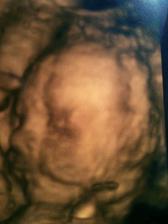

17.7.2010 dnesj jsme byli na 4D ultrazvuku..nádherný zážitek, Obě miminka se ukázala, jen Samík dělal chvilku drahoty. Jsme neuvěřitelně podobný rodičům..podle fotek z dětství je Samík celej tatínek a Vanesska celá já 🙂